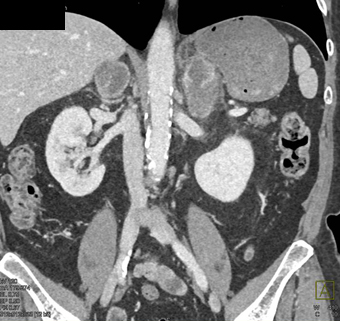

The least likely primary tumor in this case is

metastatic melanoma

lung cancer (NSCL)

colon cancer

renal carcinoma